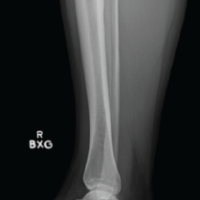

A 33-year-old housewife presented to the orthopedic outpatient of a tertiary care center with complaints of swelling in the bilateral lower leg (posterior) region with no known co-morbidity. The patient first noticed swelling 5 years ago, which was insidious in onset and gradually increased in size. Initially, it was painless, but in the past 3 months, she had been experiencing pain while squatting, which was relieved by standing or taking oral medication. Examination findings of the patient showed fusiform swelling over the left and right Achilles tendon regions, measuring 10 × 3 cm and 8 × 3 cm, respectively (Fig. 1 and 2).

Bilaterally, the swelling was firm and adherent to the underlying Achilles tendon and was moving with the plantar flexion. The overlying skin showed no erythema or ulceration, no signs of inflammation. There was no local rise in temperature, tenderness, or any neurovascular compromise. The lipid profile of the patient did not show any derangement. The patient was sent for radiographs, which showed diffuse soft-tissue swelling without bony abnormalities or calcification bilaterally (Fig. 3). Ultrasonography (USG) yielded diffuse uniform thickening of tendons with loss of normal fibrillary architecture bilaterally. Magnetic resonance imaging (MRI) showed fusiform enlargement of the entire Achilles tendon on both sides, extending from the musculotendinous junction to the calcaneal insertion. The internal heterogeneity in the lower 1/3rd of the tendon was suggestive of a high-grade partial interstitial tear and underlying myxoid degeneration. Mild edema in the fat anterior to the Achilles tendon was also noted. The patient was planned for en masse resection of the swellings bilaterally and was taken to the operating theater. Intraoperatively, en masse resection was not found to be feasible, as the swelling was completely integrated with the Achilles tendon, with no clear interface between the tendon and the pathological tissue (Fig. 4-6).